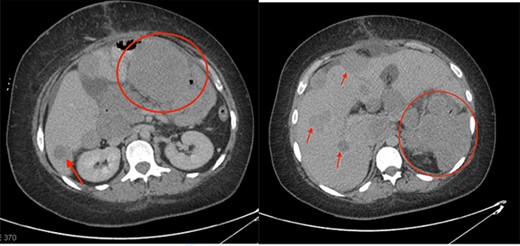

Postoperatively, her hemoglobin and leukocytosis improved (hemoglobin of 95 g/L and a WBC of 20 × 10e9/L); however, she developed a large pulmonary embolus and was placed on anticoagulation. A one-month follow-up CT scan showed progression of disease with a gastric mass measuring 6 cm, multiple enlarged mesenteric masses and enlargement of the hepatic metastases (Fig. 2). Final pathology analysis reported a malignant IMT with spindle cells mixed with patchy areas of inflammation and necrosis. The specimen was ALK and vimentin positive and pankeratin, C-kit, DOG-1, NTRK, smooth muscle actin, Melan A and HMB45 negative. The lesion had a high Ki67 proliferation index of 80–85%. She was started on Crizotinib (tyrosine kinase inhibitor), as it has shown to be effective in control of local recurrence in ALK positive IMTs [4].

One-month post-operative follow-up CT scan showing progression of disease with large metastatic deposits (indicated by the red circles and arrows).